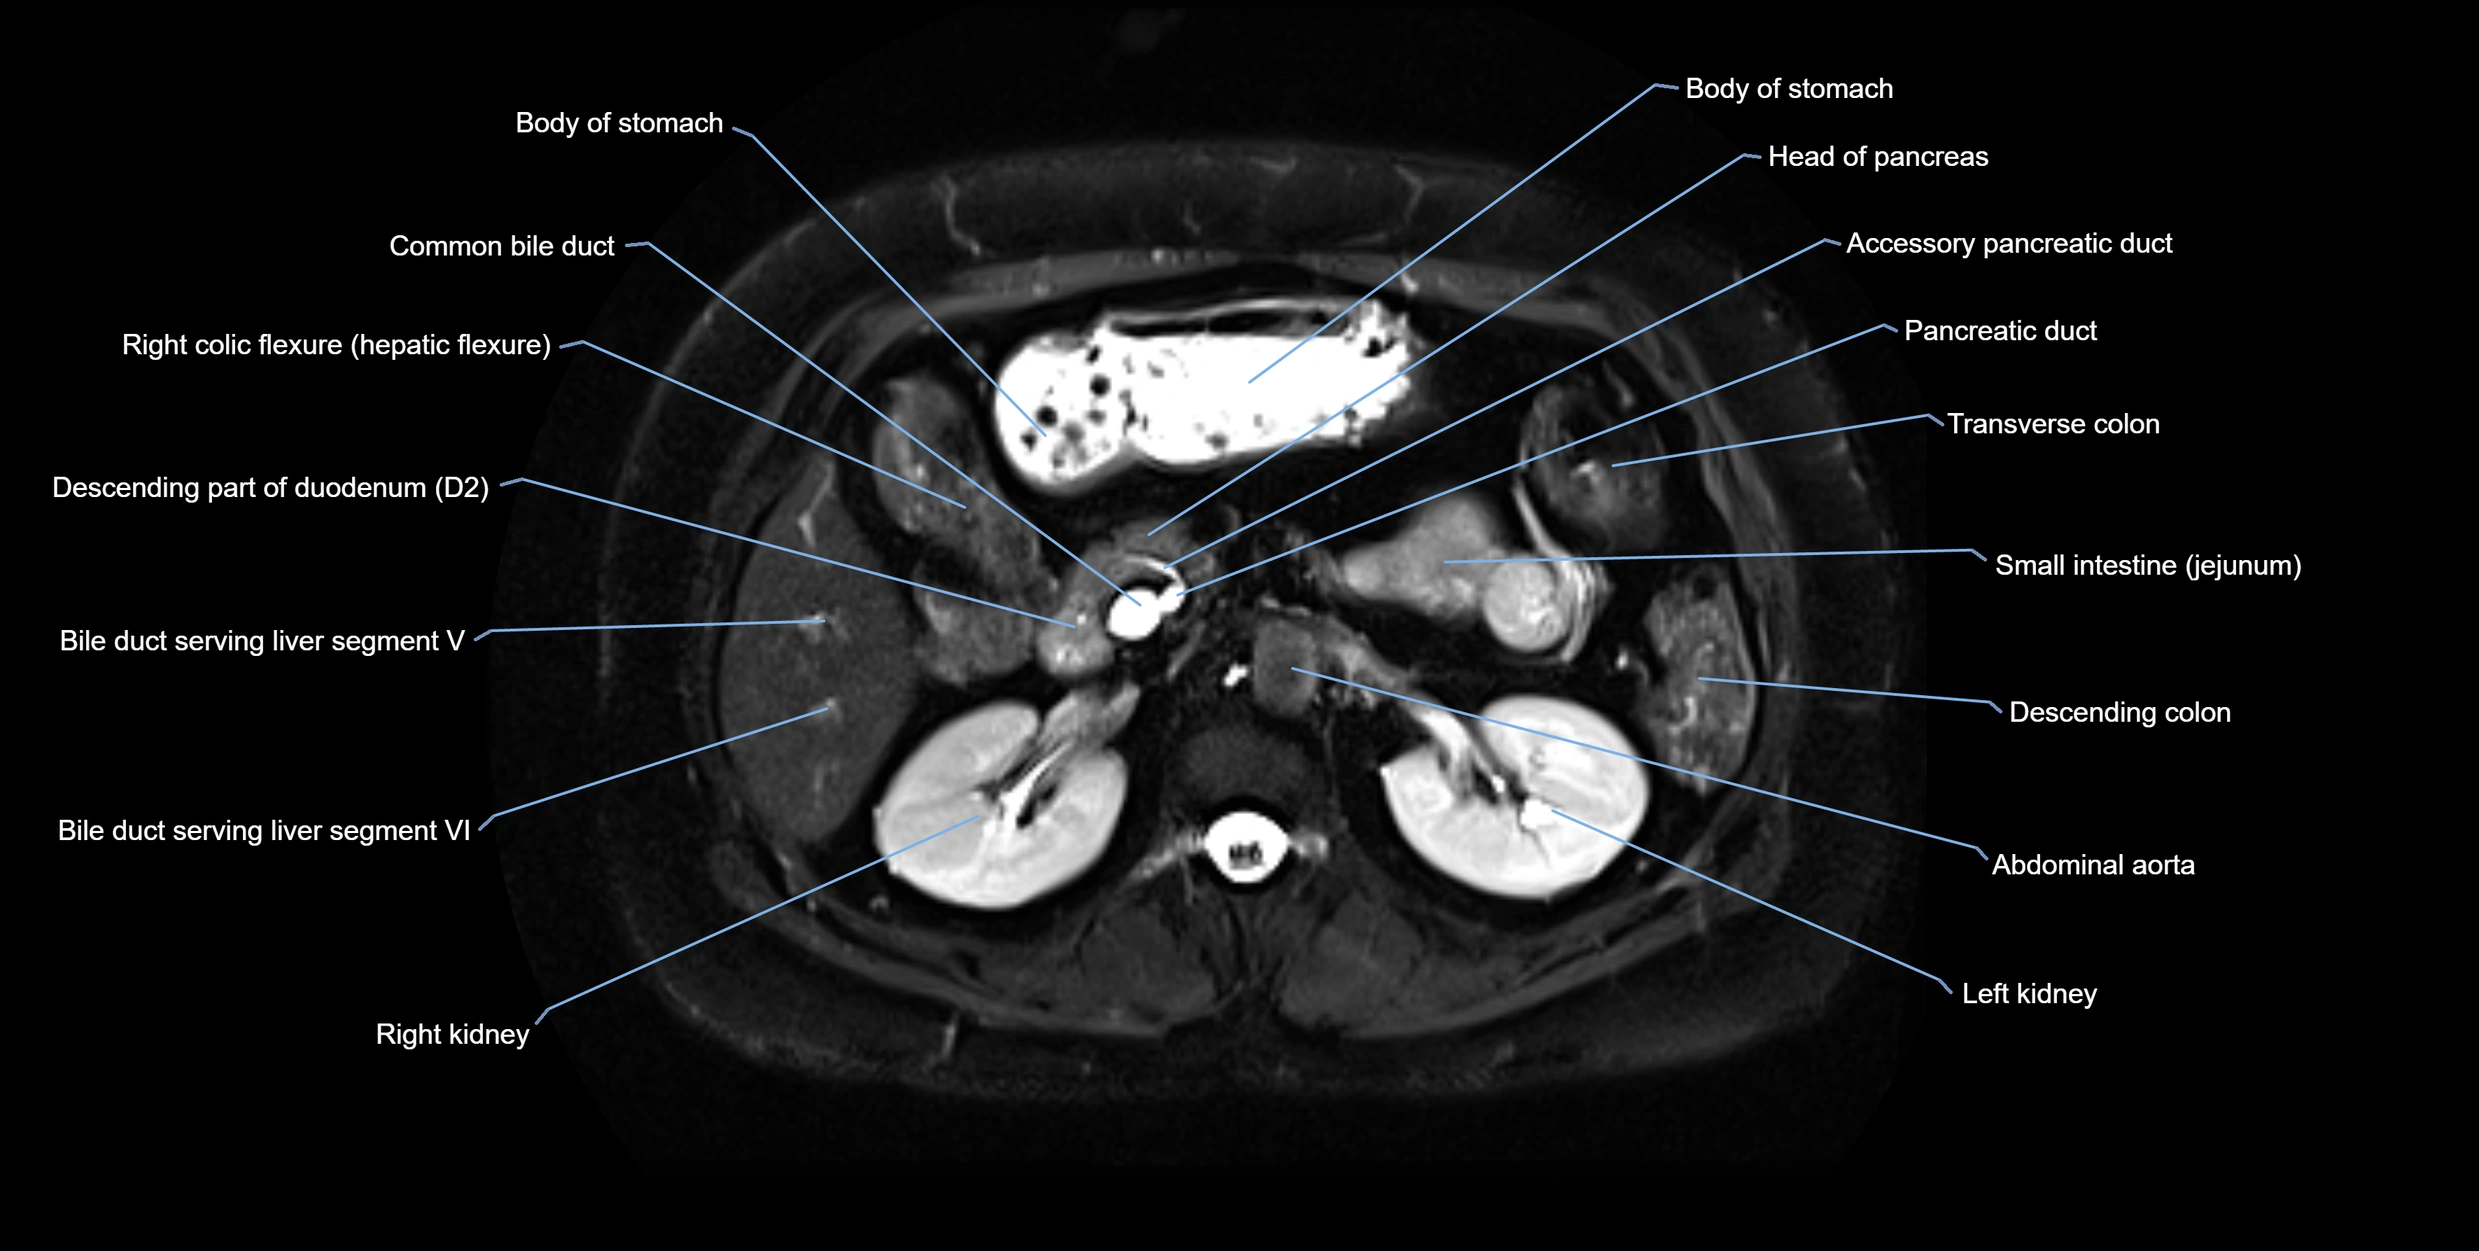

MRI Appearance

T1-weighted images:

• Not typically visualized unless dilated; appears as low signal tubular structure if seen

• Surrounding pancreatic parenchyma shows intermediate signal

T2-weighted images:

• Duct fluid appears bright

• Accessory duct seen as a fine high-signal tubular structure in pancreatic head

STIR (Short Tau Inversion Recovery):

• Duct fluid remains bright

• Surrounding fat suppressed, improving duct conspicuity

T1 Fat-Sat Post-Contrast:

• Normal duct does not enhance

• Surrounding inflammatory or neoplastic changes may enhance

T2 Fat-Saturated HASTE (single-shot):

• Accessory duct: bright, thin linear structure in pancreatic head

• Stones, strictures, or air bubbles appear as dark filling defects

• Excellent for rapid evaluation of duct patency

T2 TSE Fat-Saturated 3D (MRCP sequence):

• Duct visualized as a continuous bright tubular structure joining or parallel to the main pancreatic duct

• Allows 3D reconstruction of ductal anatomy and variants

• Excellent for diagnosis of pancreas divisum

Thick-slab T2 Fat-Saturated HASTE:

• Shows the accessory duct as part of the biliary–pancreatic system in a projectional image

• Highlights communication with main pancreatic duct and opening into the minor papilla

• Filling defects (stones, strictures) seen as dark spots within bright fluid

MRI image

image